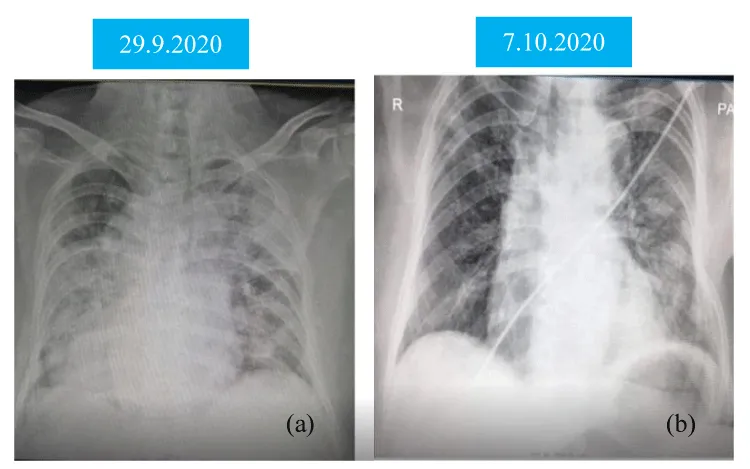

A-91-year old man had fever, cough with dyspnoea for 7 days and was brought to hospital. He was previously healthy and lived with caring family. He did not have dementia and was ambulating well. He was not diabetics nor hypertensive. His nasopharyngeal swab for Covid-19 PCR was positive. His SaO2 on air was 83% and respiratory rate was 28/minutes. Chest Xray was consistent with severe pneumonia as patchy opacities occupied more than 50% of lung parenchyma on both sides (Figure 1(a)). His total WBC was 31.6 X109/l and absolute lymphocyte count was 2.2 X109/l. He had high LDH (1262 U/L), high CRP (297.94 mg/l) and serum creatinine was marginally raised (1.6 mg%) Thus, he was treated as a case of severe Covid-19 infection with oxygen 10L/min, imipenem, azithromycin, dexamethasone, low molecular weight heparin, vitamins and dexamethasone. Convalescent plasma therapy was given on Day 12 symptom onset.

He made gradual improvement over one weeks. His symptoms improved on Day 14 symptom onset. Absolute lymphocyte count decreased to 1.5 X 109/l and Chest Xray too (Figure 1(b)). His nasopharyngeal swab for Covid-19 PCR was negative on Day 15 symptom onset.